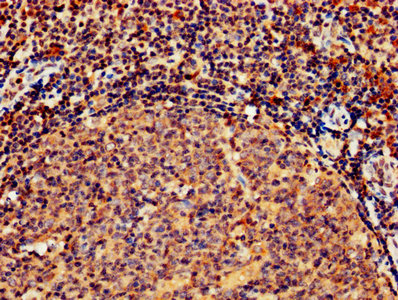

ApplicationELISA, IHC, IF; Recommended dilution: IHC:1:500-1:1000, IF:1:200-1:500